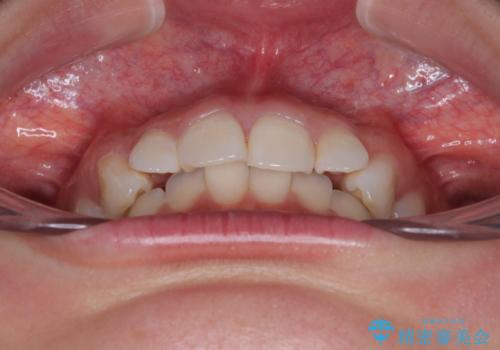

- 前歯のデコボコと突出感を気にして来院された患者様です。

極力目立たない装置を希望とのことで、インビザラインを用いて非抜歯で矯正治療を行うこととしました。

事前に親知らず2本を抜歯し、多少歯列を後方に移動できるように準備をした上で、なるべく歯と歯の間を削ることなくデコボコを解消できるように計画しました。

前歯の捻れを改善するとともに、口元が少しでも引っ込むように治療計画を立て、仕上げることができました。

長時間の装着を徹底し、遠方からの通院にもかかわらずしっかりと通院いただき、予想よりも早く治療を終えることができました。